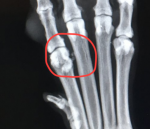

Hmmm I don't know... I know there are myriad problems that can affect feet. The vet seemed most concerned about the objects between the toes. She felt that Pops shows signs of pain when she manipulated the middle toe.I'm wondering, is that the soft tissue between the toes, and if so, do dogs get Morton's neuromas?

Poppy's toes are tight, both front and back. But she is holding her left front leg slightly out to the side now. Cortisone does not seem to have done anything; back to the vet tomorrowDo Poppy’s front toes spread out when she stands on them, or are they tightly held together?